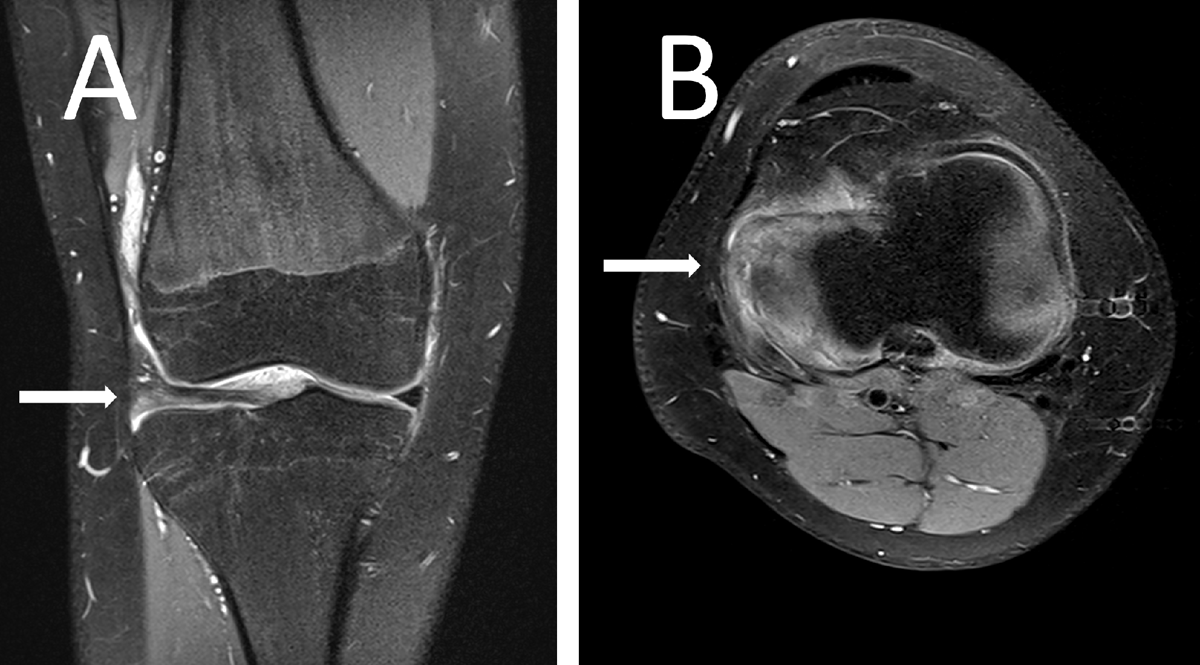

Figure 2

Proton density fat-saturated image of the boy’s knee showing a lateral discoid meniscus (arrow) in a coronal plane (A) and a complex posterior horn lesion (arrow) in of the meniscus in an axial plane (B).